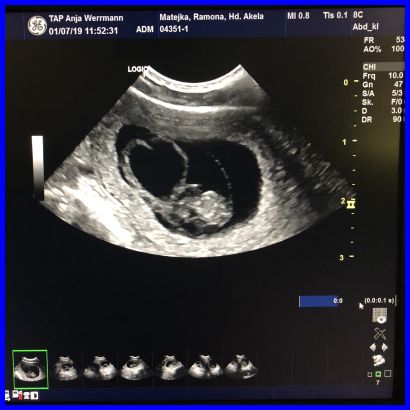

Da ist es, das erste Baby, man kann es ganz deutlich in der Fruchtblase sehen.